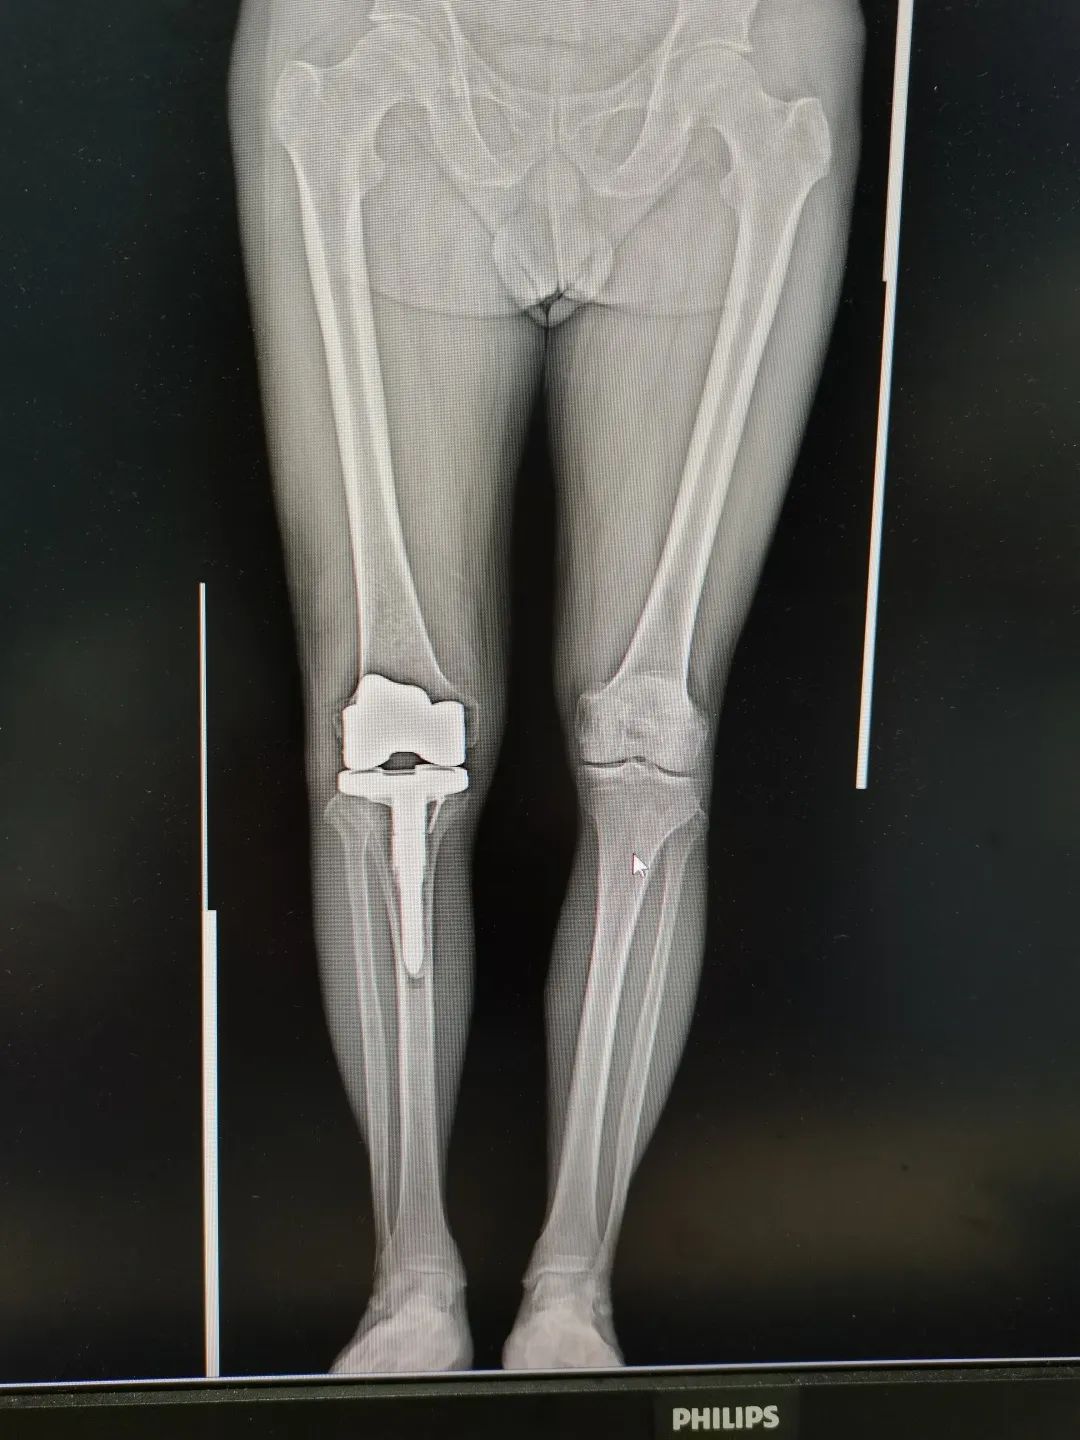

大医精诚,妙手医骨|莆田市中医医院骨科专家——刘航涛